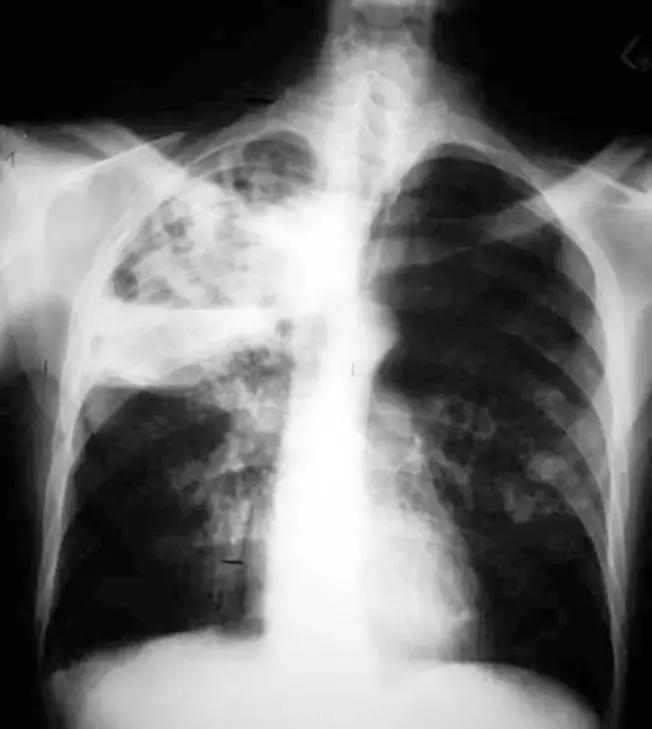

7月27日胸部CT

7月27日成功拔除气切插管;口服利奈唑胺序贯治疗;

8月1日好转出院,转回中心医院继续康复治疗。